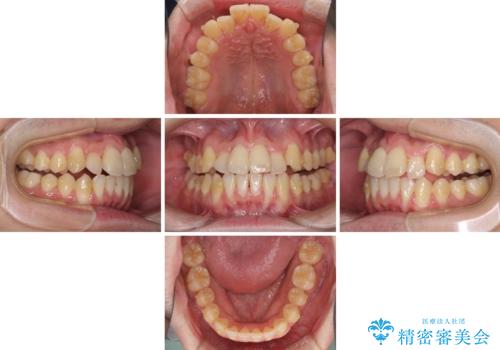

前歯のクロスバイト インビザラインによる矯正治療

- 上下のクロスバイトと前歯のデコボコを気にして来院された患者様です。

インビザラインを用い、IPR(歯と歯の間を削る)と歯列全体を拡大させることで、歯並びを整えていくこととしました。

上下ともに歯列全体を後方に移動させるため、上下の親知らずを抜歯することとしました。

奥に位置していた上の前歯が下の前歯を乗り越える際、奥歯でものを咬むことができず、辛い時期が続きました。